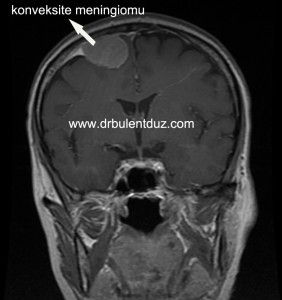

Parasagittal konveksite meningiomu ameliyatı

Aşağıdaki videoda yukarıda gördüğünüz parasagittal konveksite meningiomunun ameliyatını izleyebilirsiniz.